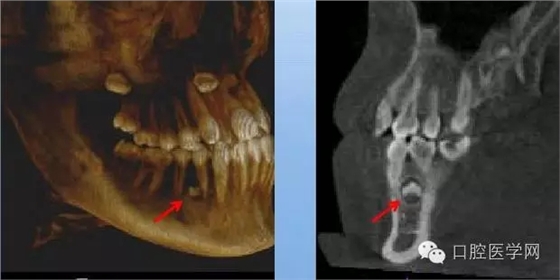

4.阻生牙

最常見于下頜第三磨牙

X線表現(xiàn):確定阻生牙的位置;確定阻生方向;牙根數(shù)目和形態(tài);阻生牙有無齲齒和根尖情況;與第二磨牙的關(guān)系;與下頜管的距離和磨牙后間隙的大小。